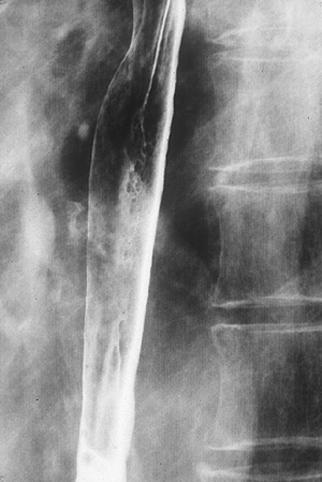

Criteria of Hist.ClassificationMalignant epithelial tumor/Squamous cell carcinoma

LocationEsophagus/Middle third

Technique, MethodX-ray

Macroscopic TypesType 0/IIc (IIc+IIb) Superficial depressed and flat type

Size40 -

Depth of Tumor Invasionmuscularis mucosa